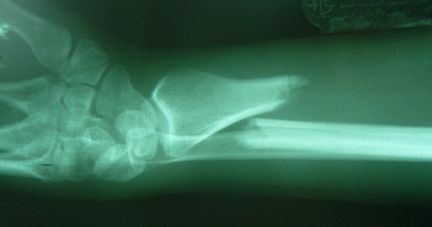

| Back in Tampa, I ordered films of Alison's arm for presentation to her orthopedic surgeon. | |

| Alignment is not perfect, but I was told that closed reductions involve a bit of luck, and no ground has been lost because healing does not commence for a few weeks. After a curbside conference, he indicated that the best plan for optimal alignment and minimal cast time would be a plate and screws, usually not palpable or visible from the outside after healing. | |